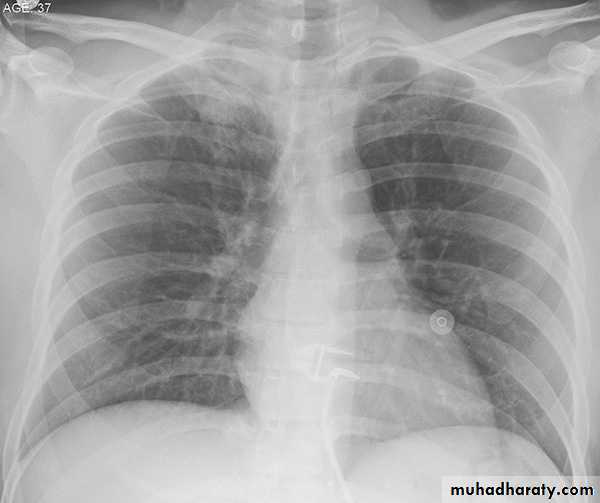

Radiological investigation of a 78-year-old man with a six-week history of productive cough, fever, left-sided chest pain, dyspnoea on exertion and hoarse voice . (a) Chest x-ray and (b) CT scan showed (c) a soft tissue mass in the left upper lobe that encased the left upper lobe bronchus. (d) A chest x-ray performed at the end of TB treatment showed a significant resolution of the initial consolidation seen in the left upper lobe, persistence of the mass (diagnosed as being carcinoid tumour), left upper lobe fibrosis, loss of left lung volume, a left pleural effusion and a large heart shadow